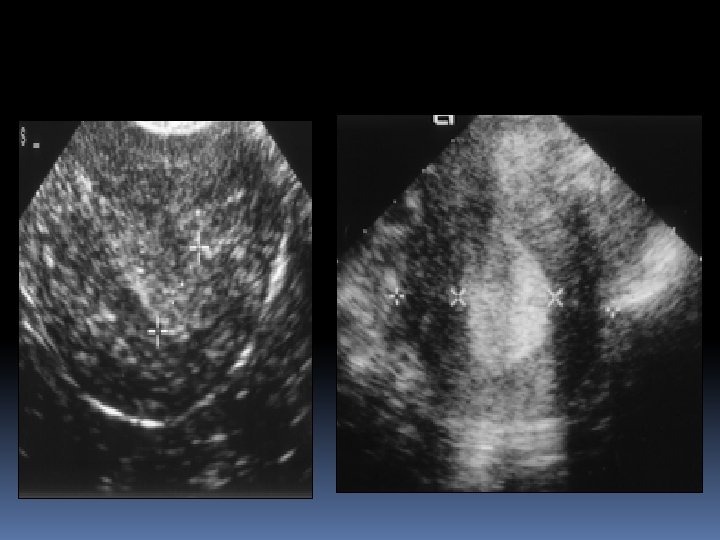

Diagnosis The mainstays of diagnosis are Transvaginal ultrasound scanning; endometrial thickness of less than 4 mm, cancer is very unlikely, any measurement more than this will require further assessment. Endometrial biopsy by the Pipelle or by Dilatation & curettage Hysteroscopy directed biopsy MRI is often performed: (for staging) and helps to decide on the type of surgical treatment